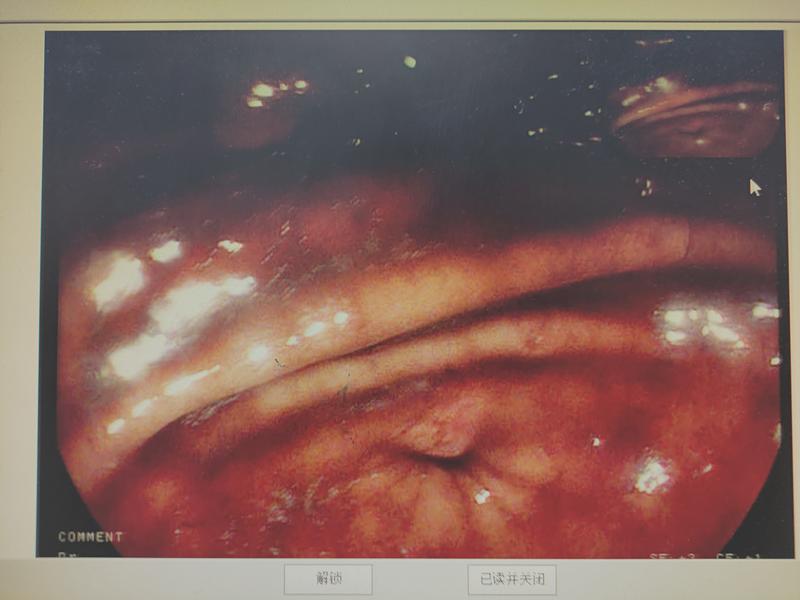

满视野大量血迹

发现罪犯血管活动性出血

胃底

大量新鲜血液及血凝块,翻转胃镜见贲门下近胃体小弯局部见搏动性活动性出血灶,予以血管夹1枚夹闭止血,观察3分钟,未再见活动性出血。